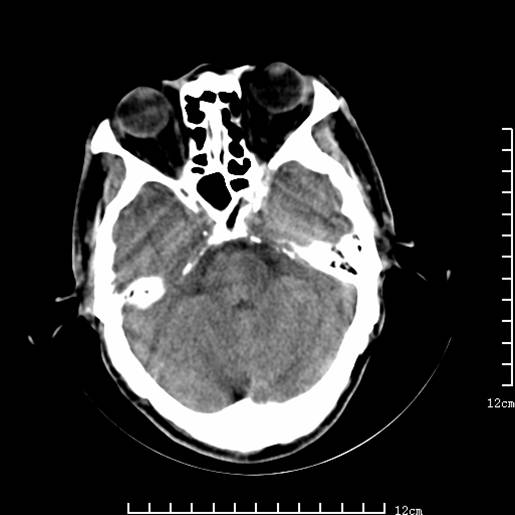

以下图像分别是3月25日凌晨及下午图像、3月27日、4月16日的ct图像。

4月16日

4月16日ct复查:符合出血性脑梗塞表现。

资料齐全,符合脑梗塞溶栓治疗后,血管再通而致的出血性脑梗塞。

支持出血性脑梗塞,可能因血管再通后,再灌注损伤所致。

4月16日ct复查:符合出血性脑梗塞表现